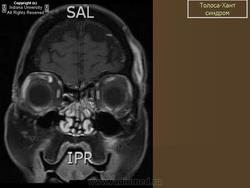

Синдром Толоза - Ханта: неврологический хамелеон

Синдром Толоза - Ханта (СТХ, болезненная офтальмоплегия, синдром верхней глазничной щели) впервые описан испанским неврологом E. Tolosa в 1954 г. и дополнен английским врачом W. Hunt в 1961 г. [6, 15]. Эта патология проявляется поражением структур, проходящих через верхнюю глазничную щель (глазничная артерия и вена, отводящий, блоковый, глазодвигательный нервы, первая ветвь тройничного нерва), и прилегающего к ней кавернозного синуса. Клиническая картина СТХ характеризуется болями чаще в области орбиты, диплопией, экзофтальмом и хемозом, которые проявляются в различных сочетаниях и бывают разной степени выраженности [7, 8, 13]. Практика показывает, что сходные клинические признаки наблюдаются при широком круге неврологических и соматических заболеваний: бактериальном, вирусном и грибковом воспалении наружной стенки кавернозного синуса или мозговых оболочек; первичных либо вторичных опухолях мозга и орбиты; сосудистых мальформациях и диссекциях ветвей внутренней сонной артерии; тромбозе, лимфоме, эпидермоидных кистах кавернозного синуса; орбитальном миозите, саркоидозе, гранулематозе Вегенера, некоторых заболеваниях крови, офтальмической мигрени и др. [1-3, 5, 12, 14].

Таким образом, в основе формирования СТХ лежат различные причины, которые определяют многоликий характер заболевания. В природе подобный аналог разнообразия назван хамелеоном. За последние годы достигнут несомненный прогресс в понимании механизмов развития этого заболевания. Cогласно критериям, разработанным International Headache Society (2004), диагноз СТХ обоснован в случаях выявления гранулемы наружной стенки кавернозного синуса при магнитно-резонансной томографии (МРТ) головного мозга либо при проведении биопсии [10]. При отсутствии изменений на МРТ более правомочен термин «синдром верхней глазничной щели», и в этих случаях пациенты нуждаются в динамическом наблюдении.

В последние годы в диагностике СТХ большую роль отводят методам нейровизуализации, так как проведение биопсии транссфеноидальным доступом обычно ограничено. T. Ozawa et al. [11] предложили МРТ-критерий СТХ: наличие в стенке кавернозного синуса патологической ткани, изоинтенсивной в Т1w-режиме и изогипоинтенсивной в Т2w-режиме. По данным La L. Mantia et al. [10], воспалительная инфильтрация или гранулемы в области кавернозного синуса при МРТ обнаружены в 44 (35 %) из 124 случаев СТХ. T.L. Haque et al. при МРТ выявляли маленькие очаги, примыкающие к краниальным нервам без распространения на кавернозный синус. При проведении МРТ в динамике после приема глюкокортикоидов авторы обнаруживали полное исчезновение очагов, что позволяет предположить их гранулематозный характер [4].